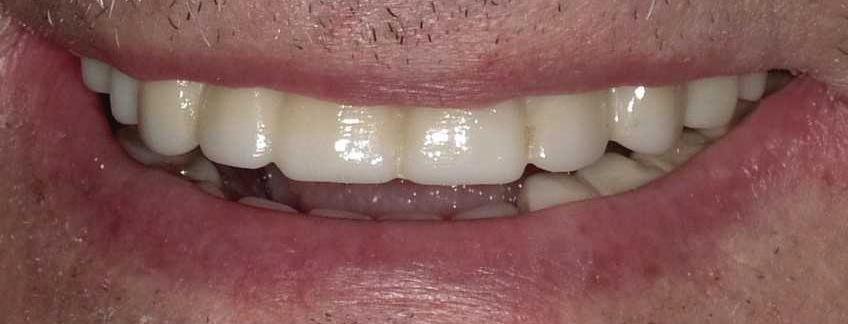

11 | Do I Need A Periodontist? | By Karl A. Smith, DDS, MS 12 | Your One-Stop Solution For a Healthy Smile | Submitted By Total Dental Care 13 | Chiropractic and Exercise For Optimal Health | By Alicia Kovach, DC 13 | Can Burn Wounds Bleed? | By Paul Samakow, Attorney 14 | TMJ Disorder and Exercise | By Jeffrey L. Brown, DDS 16 | All-On-Four Dental Implants | Submitted By Sivakumar Sreenivasan, DMD, MDS

18 | Discover Your Perfect Full Arch Dental Solution | By Judy Yu, DMD, MBA

Discover Your Perfect Full Arch Dental Solution

Embrace Comfort and Affordability

In the past, individuals missing multiple teeth had limited options beyond uncomfortable and ill-fitting dentures. However, with the introduction of dental implants, removable dentures have become a viable choice. Although dentures may require adhesives and fall short of replicating the natural form and function of teeth, they offer affordability and easy removal for cleaning.

Four Implant Overdenture

Secure and Functional

Your dental arch, whether on the top or bottom, plays a crucial role in your oral health. When the majority of your teeth are missing or reach a point where replacement is recommended, a full arch replacement becomes necessary. Fortunately, there are more options available now than ever before for comprehensive full arch treatment.

Removable Dentures

Stabilized overdentures resemble traditional removable dentures, but with a significant improvement in stability. By utilizing four locators on the underside of your denture plate, they securely attach to implant abutments. These snap-on dentures eliminate rocking, shifting, or rubbing, as the implants keep the appliance firmly in

Please see “Full Arch,” page 61